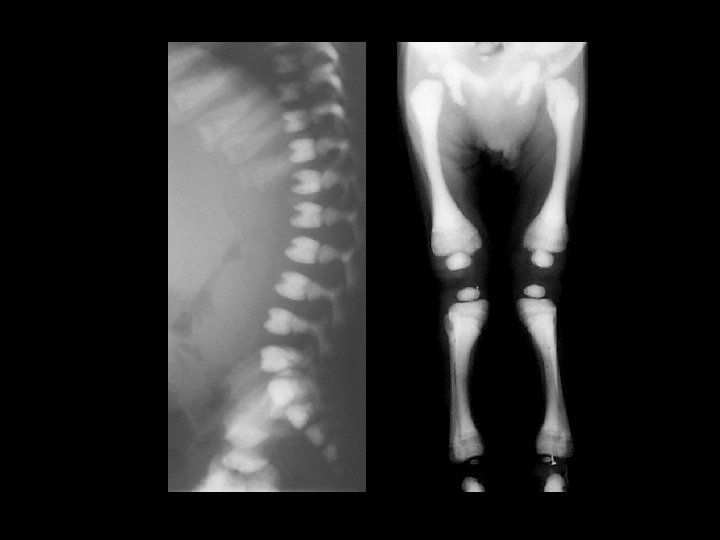

Rickets • Findings: – Cupped and frayed metaphyses – Wide physes (increased osteoid) – Long bone bowing – Decreased bone density • ddx: – NONE! – This is an Aunt Minnie!

Renal osteodystrophy • Findings: – Osteopenia – Prominent trabecular pattern – “rugger jersey” spine • ddx: – NONE! – This is an Aunt Minnie!